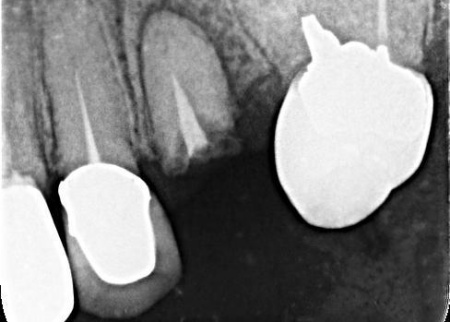

| 診断 | 拝見したところ、左上奥歯(第2小臼歯)1本が折れ、歯根だけの状態になっていました。 レントゲン撮影をして詳しく検査した結果、治療して温存することは困難な状態だったため、残っている歯根を抜き、欠損部分を補う治療が必要だと判断しました。 患者様は、人工歯根であるインプラントによる治療を希望されていましたが、レントゲン撮影の結果では、インプラントを入れるために必要な骨の量が足りていません。 以上のことから、まずは慎重に治療方法を検討する必要があると診断しました。 |

| 行ったご提案・治療内容 | 患者様には、折れた左上奥歯は温存ができず、歯根を抜く必要があることをお伝えしました。 そのうえで、希望されているインプラント治療を行うために必要な点を説明しています。 ・インプラント治療に必要な骨の量を確保するための「骨補填」を行う こちらに同意いただき、3ヶ月後からインプラント治療を始めることになりました。 まず、左上奥歯を抜きます。 3ヶ月後、顎の骨の状態が良好であることを確認し、インプラントを埋入する手術を実施しました。 |

治療前